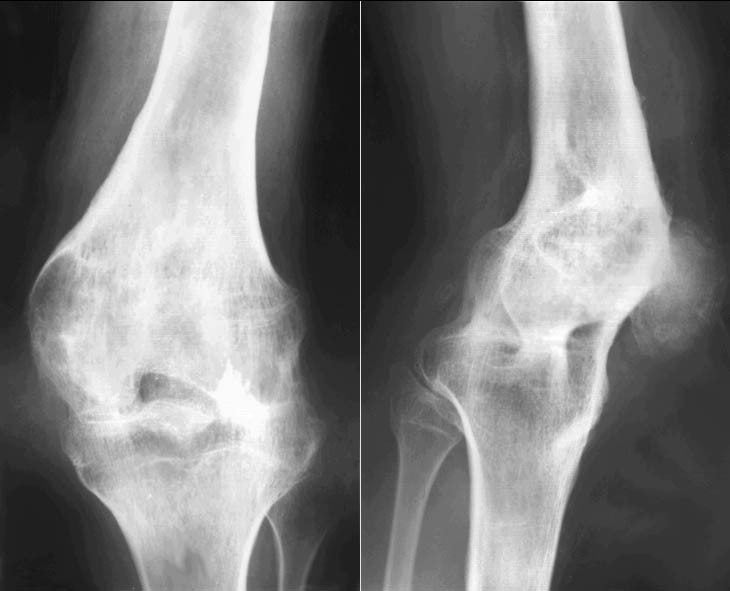

Болезнь «съедает» здоровые хрящи с разной скоростью, в зависимости от уровня физической подготовки, иммунной устойчивости, сопротивляемости организма. В первые несколько месяцев при своевременном обращении к терапевту ситуацию можно стабилизировать (не ликвидировать очаг, а остановить разрушительное движение). В любом случае терапия – не панацея, а только отсрочка. Недоедание, стресс, вредные привычки – гарантия, что рано или поздно понадобится эндопротезирование суставного сегмента. На фото стадии артроза колена выглядят так: